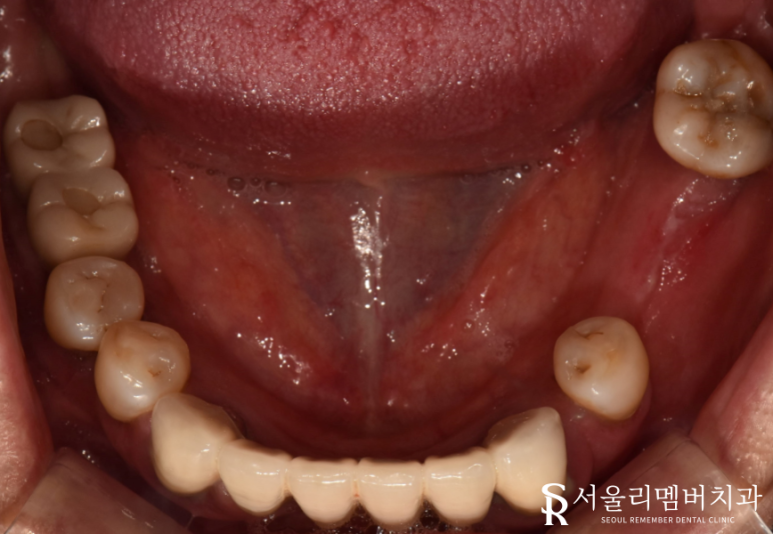

남아있는 잔존 치근, 염증이 생긴 이들을 깨끗하게 제거했습니다.

조금이라도 남아있게 된다면 또 다시 우리를 괴롭힐 수 있기 때문에 몇 차례 확인을 했죠.

자, 이제 본격적인 식립 과정으로 들어가야죠?

정확한 위치에 단단하게 심어주었습니다.

구강 상태가 좋지 않았던 거에 비해

다행히 골융합은 그리 나쁜 편이 아니네요.

별문제 없이 임플란트를 심을 수 있었습니다.